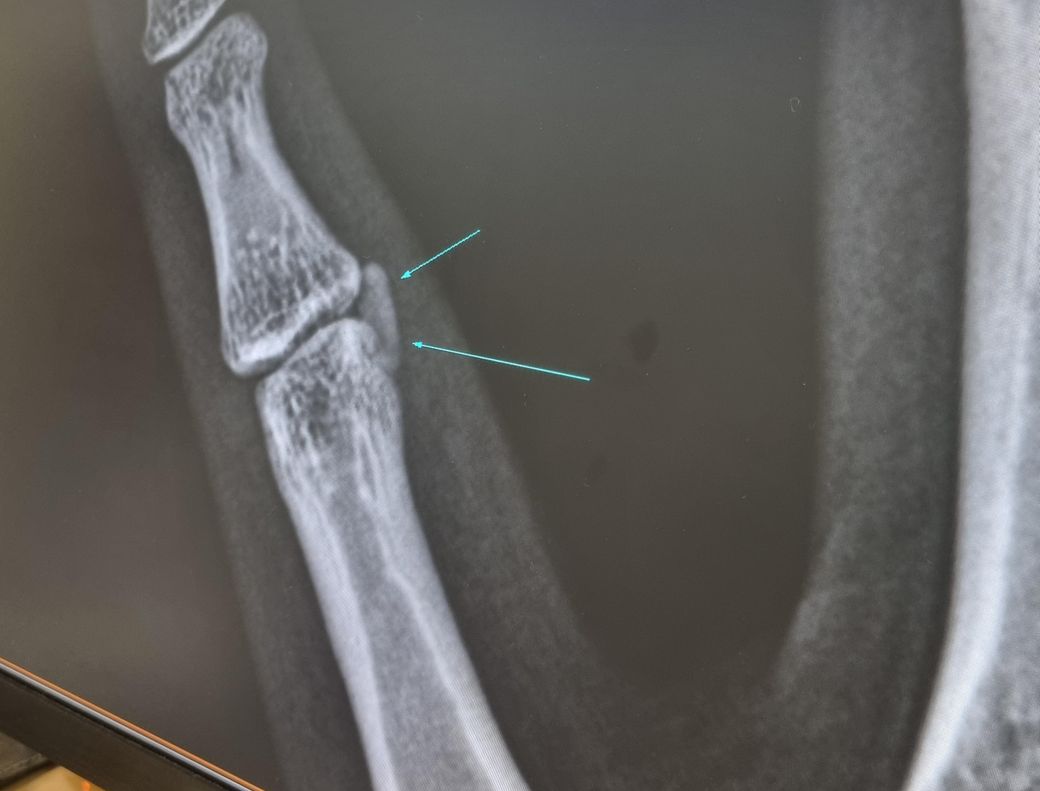

전에 석회가 꼈던 새끼손가락이 푸르게 변했습니다. 두달 전에 새끼손가락에 석회가 끼어 아파서 정형외과에 갔었는데 약 처방받고 스테로이드 주사 맞으니 일주일만에 좋아져 이후 약복용은 안하고있습니다. 근데 두어달이 지난 지금 통증은 전혀없는데 새끼손가락의 관절부분이 푸르게? 붉게? 멍이 든것 처럼 변했습니다. 무슨 문제가

생긴걸까요? 병원에 가보는게 좋을까요?

• 1번 째 사진

• 2번 째 사진